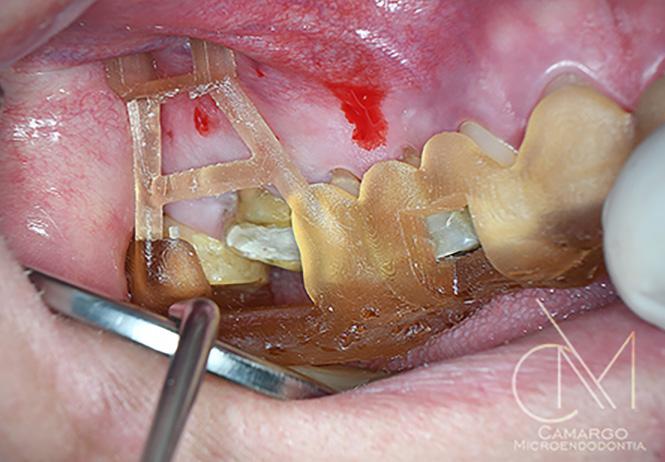

Los dientes anteriores (n.º 13 23) se feru lizaron con una férula periodontal Rib bond, y la oclusión se ajustó a un contac to ligero. Se elevó un colgajo de espesor total, y el defecto se descontaminó con una combinación de láser de CO2 de 9,3 micras y EDTA al 24 %. Después de la descontaminación confirmamos un de fecto de una pared con una bolsa perio dontal intraósea de 7 mm. Injertamos el defecto con Geistlich Bio‑Oss® Collagen, que tiene una excelente capacidad para actuar como andamiaje y resulta muy útil en esta indicación.1 Después cubrimos el injerto óseo con L PRF™ para una mejor respuesta angiogénica de los tejidos.

| A Antes del tratamiento ortodóncico. | B CBCT periapical antes del tratamiento periodontal. | C Dientes (13 y 23) ferulizados. | D Bolsa intraósea de 7 mm después de abrir el colgajo. | E Geistlich Bio-Oss® Collagen rellenando el defecto. | F Membrana L-PRF™ bioactiva cubriendo el injerto óseo. |

Fotografías: Scott Froum Fotografías: Scott Froum FIG. 1: Un caso de tratamiento regenerativo de dientes insalvables.